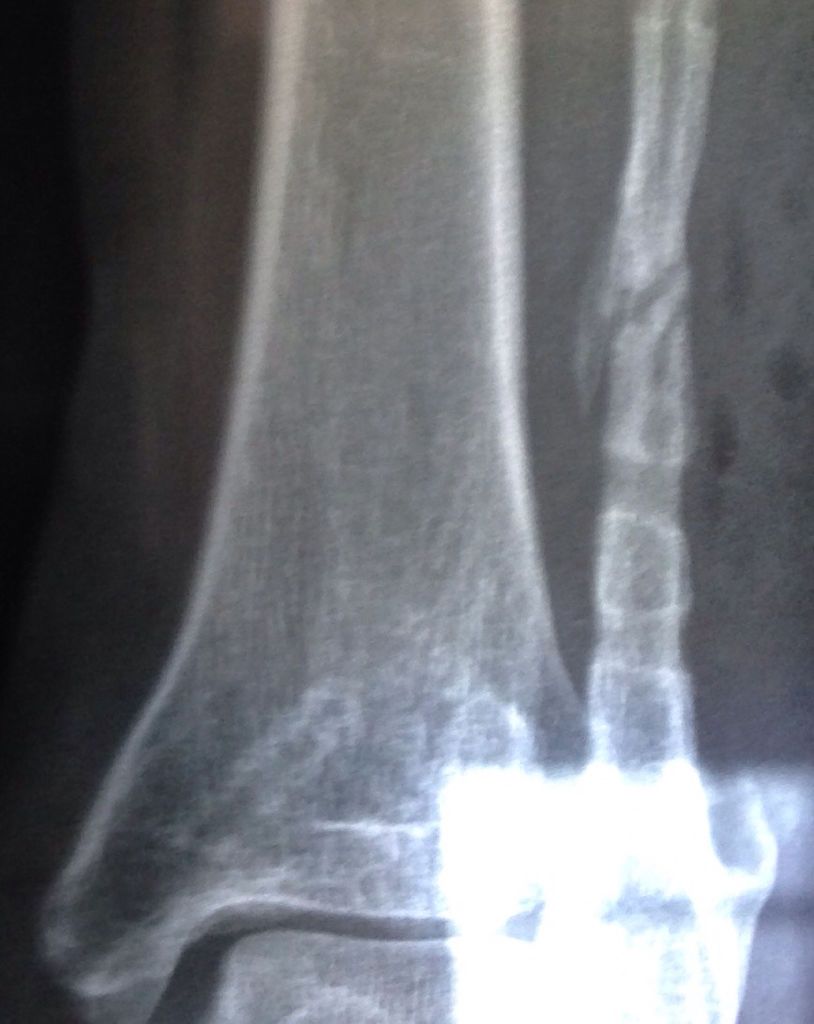

腓骨不愈合 我今年34岁,十九个月前腓骨骨折,做了内固定,现在骨折端硬化了,骨腔大部分闭塞了,前几 腓骨不愈合 我今年34岁,十九个月前腓骨骨折,做了内固定,现在骨折端硬化了,骨腔大部分闭塞了,前几天把钢板拆出来了,医生说不拆也不能好了,拆出来看看能不能通过骨膜成骨,有朋友能给个好建议我么?现在这种情况要怎样处理最好? 点击展开 匿名用户 2015-08-21 10:26 满意回答 我它助考虑十有八九是手术时骨唤认膜剥离过多,重新打通骨髓腔怪逝且,再长吧! 匿名用户 2015-08-21 10:33 宝宝知道提示您:回答为网友贡献,仅供参考。 为您推荐: 其他回答 拆了~安心躺床上养个月把~就好了 匿名用户 2015-08-21 10:30 相关问题 腓骨远端骨折已4个多月,骨折已愈合 但现在仍不能正常… 腓骨骨折 之前恢复很好 术后七个月后鼓起一包裂开并伴有脓液流出 久不愈合 左股骨颈骨折九个月愈合后多久可以脱拐?45

腓骨不愈合 我今年34岁,十九个月前腓骨骨折,做了内固定,现在骨折端硬化了,骨腔大部分闭塞了,前几天把钢板拆出来了,医生说不拆也不能好了,拆出来看看能不能通过骨膜成骨,有朋友能给个好建议我么?现在这种情况要怎样处理最好?